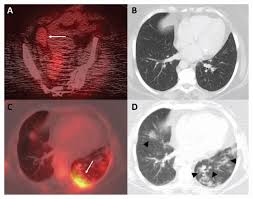

최첨단 현대의학으로 가장 적절한 방법이 양전자단층촬영술(Positron Emission Tomography, PET)이라고 나는 생각한다. PET는 체내 대사 변화를 촬영하는 기기로 CT나 MRI 다음에 개발된 영상장비이라고 한다.

요즘은 여기에 CT를 붙여서 PET 영상과 CT 영상을 융합해 서로 약점을 보완해 검사의 질을 더욱 높이고 있다고 한다.

여기에 방사성 핵종 F-18를 붙여(F-18 FDG라고 함) 혈관 주사하면 빨리 자리는 암세포는 포도당이 더 필요해 정상 세포보다 10∼100배 더 많이 모여들고 이를 방사능으로 촬영해 찾아낸다. 암이 1㎝만 돼도 10조개의 암세포가 있어 CT, MRI 소견이 애매한 경우 유용하게 쓰인다.

물론 PET도 아주 작은 암은 놓치기도 하지만 대체로 약 0.5㎝ 이상의 암은 거의 80% 찾아내고 있다고 한다.

또 부수적으로 뇌 부분의 PET 영상으로 분석해 뇌졸중, 알츠하이머 치매도 조기 진단할 수 있다고 한다. 검사도 간단해서 정맥 주사를 맞고 1시간대기 후에 20분 정도 누운 상태로 촬영한다.